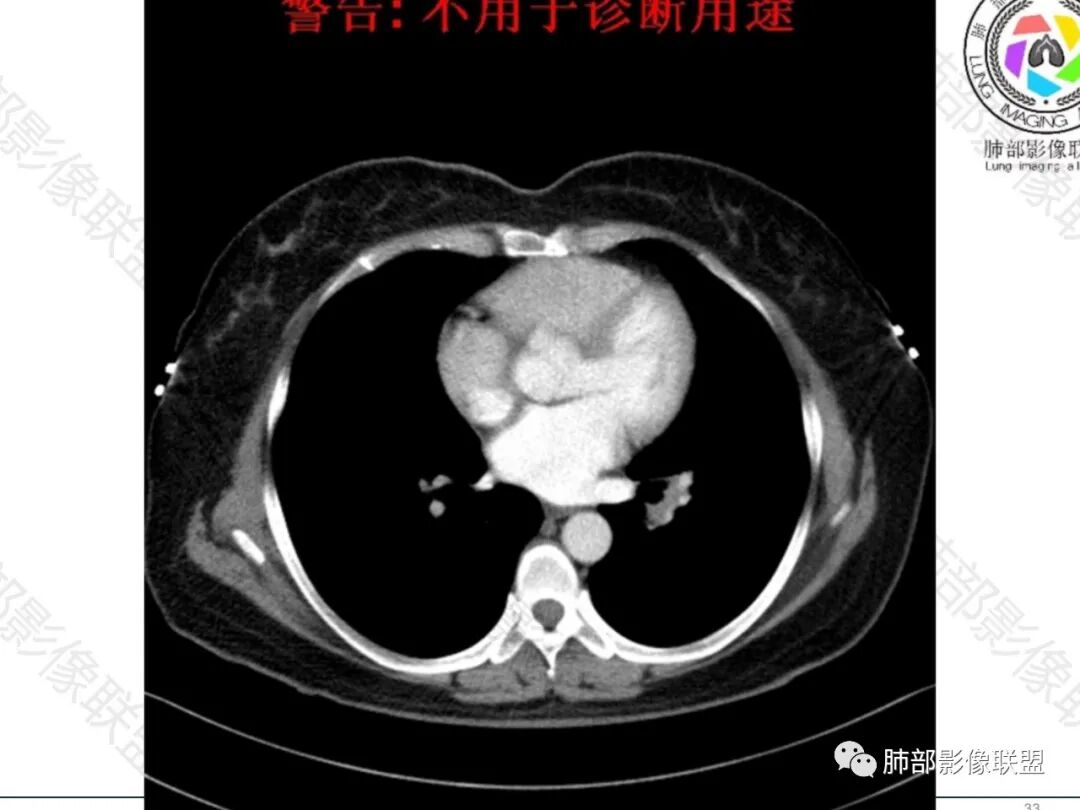

如果是结节病的话,应该是2期了,但淋巴结的境界总感觉不那么清楚,结节病的淋巴结大多清晰不融合。

是的,结节病的淋巴结多数不融合

中年女性,轻咳,乏力,影像表现:左肺门淋巴结肿大融合,血管无明显侵犯,支气管呈针孔样改变,远端支气管复出无异常,纵隔及主动脉旁多个稍大淋巴结显示,右乳结节。肺内小叶间隔增厚伴疑似小结节样改变。

一、恶性病变:1、小细胞肺癌,左肺门淋巴结肿大融合,针孔样支气管伴远端复出,要考虑,但肺内无见原发灶存疑,2、淋巴瘤,淋巴结肿大融合,肺内小叶间隔增厚,要考虑,但单侧淋巴结肿大融合相对少见一些。3、转移,多发淋巴结肿大伴肺内小叶间隔增厚,要考虑。需要结合有无肿瘤史,以及肿瘤标志物综合分析。4、乳腺癌伴转移,右乳结节更象良性结节,且纵隔淋巴结以左侧为主,不支持。

二、良性病变:1、结节病,淋巴结肿大伴肺内小叶间隔增厚,肺内疑似小结节,必须考虑,但单侧淋巴结为主的相对少见一些。而且引起支气管针孔样改变的也较少。2、结核,有轻咳,乏力,淋巴结肿大,支气管变细,要考虑。但肺内无明确结核灶,可能性小一些。

综上所述:小细胞癌>结节病>淋巴瘤,结核与转移可能性小,下一步,查肿瘤标志物及TBLB或EBUS穿刺活检。

这个左侧支气管在纵隔淋巴结内穿行时,明显变细变小了。

结节病一般很少挤压这么明显的。

还是结节病啊,

觉得单侧,肺内小叶间隔增厚的结节少见,以后还是要警惕啊

单侧的我见过一些,但淋巴结质感好像都比较硬,

说是单侧,其实往往在一个阶段表现为单侧

尘缘:

这个结节病除了肺内小叶间隔增厚及疑似小结节比较支持外,单侧淋巴结肿大,质感较硬,支气管挤压太明显,都比较难,但还是要考虑的